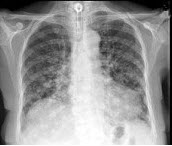

40、单项选择题

女,67岁,咳嗽1周,有甲状腺癌史,结合胸片,最可能的诊断()

A.甲状腺癌肺转移

B.粟粒型肺结核

C.尘肺

D.结节病

E.肺炎